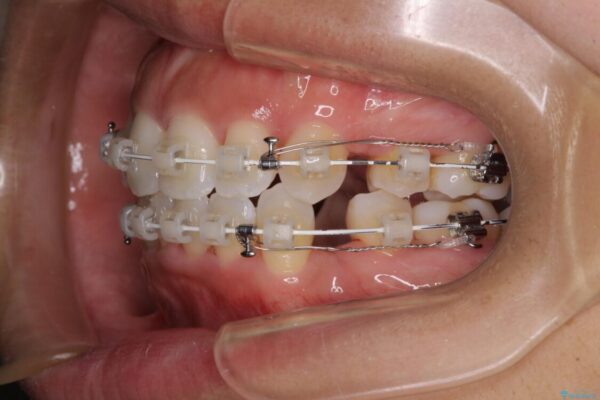

治療途中

• 抜歯矯正で唇を閉じやすく 目立たないワイヤー装置 治療途中画像

上下顎ともに前突した歯列であったので、上下ともに左右の第1小臼歯4本を抜歯し、ワイヤー装置にて矯正治療を行うこととしました。